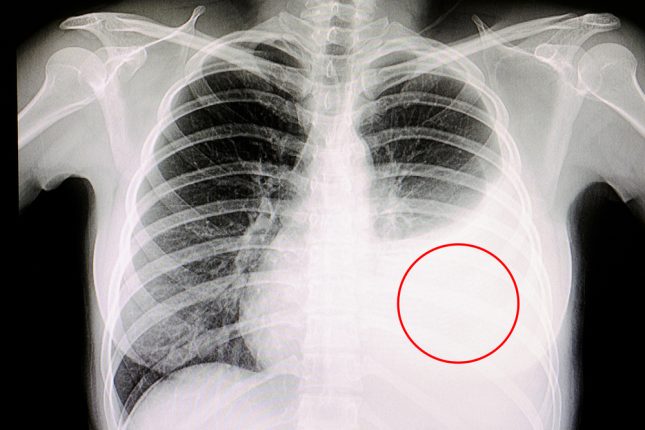

זרוע A: מטופלים עם התעבות פלאורלית או נגע נוסף על תפליט פלאורלי. ממטופלים אלה נלקחה דגימה מהפלאורה בעזרת מחט אבראמס בהנחיית CT.

זרוע B: מטופלים עם תפליט פלאורלי בלבד או חשד למחלה שפירה כתוצאה מאסבסט. קבוצה זו עברה תורקוסקופיה רפואית (MT).

זרוע C: מטופלים עם התעבות פלאורלית בלבד. מקבוצה זו נלקחה דגימה בעזרת מחט חותכת בהנחיית אולטרסאונד.